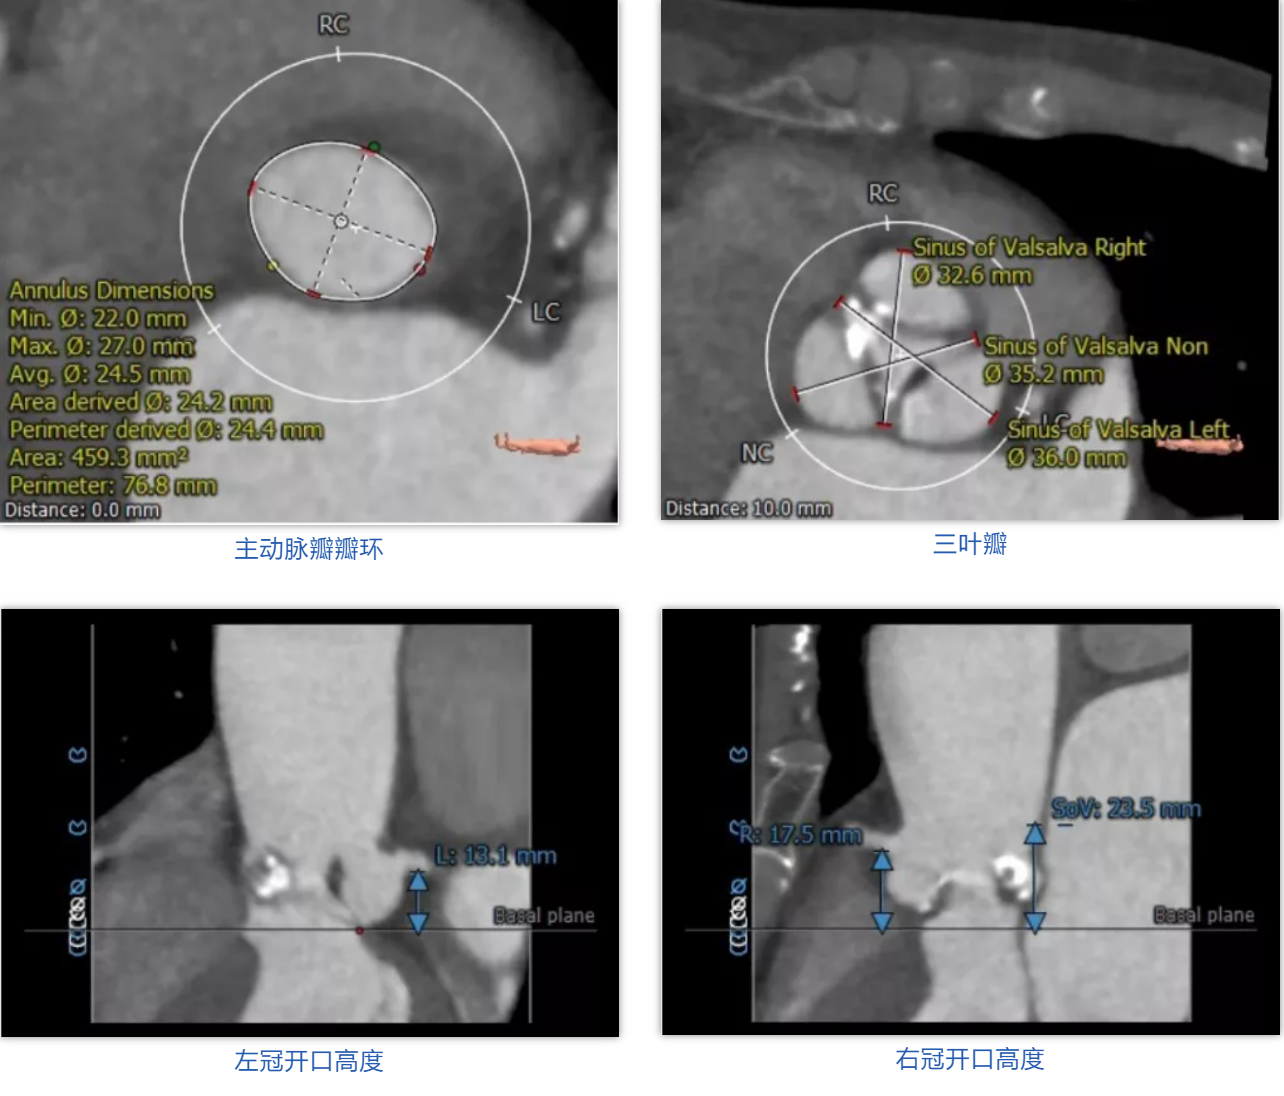

病例1

患者女性,71岁。术前心脏超声提示主动脉瓣瓣叶钙化,重度狭窄,轻度反流。CT评估结果显示主动脉瓣为三叶瓣,瓣叶钙化,瓣环平均直径24.4mm,瓣环面积459.3mm²,面积径24.2mm。左冠脉开口高度13.1mm,右冠脉开口高度17.5mm。术前经详尽影像学重建、评估及病例讨论,测量瓣环直径,评估冠脉梗阻风险后,计划植入 25# Renatus介入主动脉瓣。